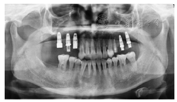

像(4)种植:2013年11月,牙周复查显示牙周状况稳定,开始行

种植术,植入4.3 mm×10.0 mm植体5枚(Nobel Replace,瑞典),

同期GBR植骨(图8)。2014年2月,取模制作临时冠,作为正畸支抗继续正畸治疗。2014年11月,拆除固定矫治器,制作保持器,牙周复查情况稳定(图9,图10)。